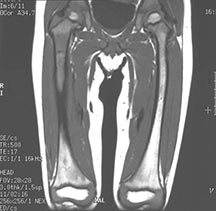

- May arise from any bone and any site within a bone (epiphyseal, metaphyseal, diaphyseal)

- Radiographically variable appearance: may appear benign (geographic) or malignant (permeative or moth eaten)

- Flat Bones (most common—70%)

- Femur